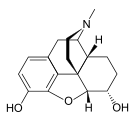

Natural opiates

Opium alkaloids

Structures

| Morphides | ||||

|---|---|---|---|---|

Codeine Codeine |

Morphine Morphine |

Oripavine Oripavine |

Pseudomorphine Pseudomorphine |

Thebaine Thebaine |